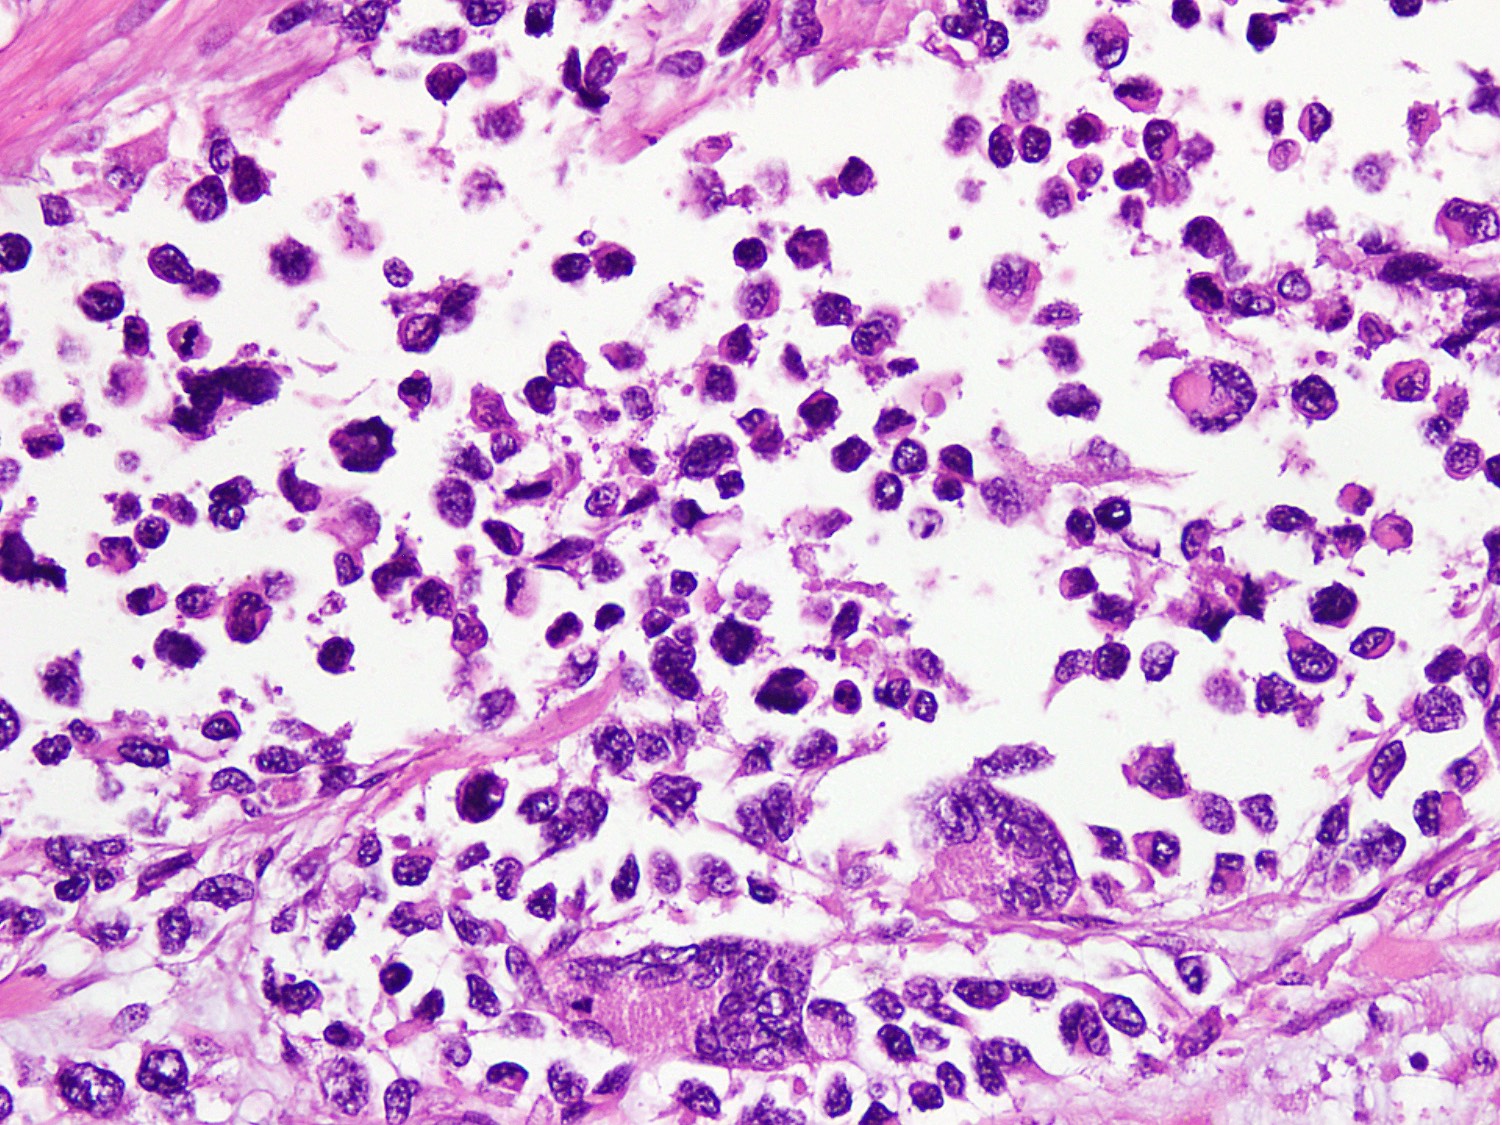

Microscopic (histologic) description

- Cellular round cell tumor

- Large clusters, nests, cords and trabeculae of primitive round cells, separated by variably thick fibrovascular septa

- Loss of cellular cohesion in the center forms alveolar-like, cystic and vague papillary appearance (Histopathology 2022;80:98)

- Layer of cells adheres to the periphery of the spaces and fibrous septa

- Small to intermediate sized monomorphic cells with scant cytoplasm

- Hyperchromatic nuclei with variable conspicuous small nucleoli

- Cells in the center have poor preservation and are necrotic; may appear floating

- Multinucleated tumor giant cells with wreath-like lineup of nuclei are common (Acta Pathol Microbiol Immunol Scand A 1982;90:345)

- Round to oval rhabdomyoblasts with abundant acidophilic cytoplasm may be present

- Brisk mitosis and variable tumor necrosis

- Occasional cases may show clear cell morphology with pale, glycogenated cytoplasm

- Rare anaplasia

Microscopic (histologic) images

Contributed by Nasir Ud Din, M.B.B.S.